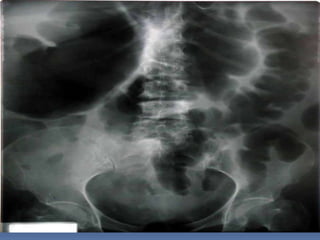

PROYECCION SIMPLE DE

ABDOMEN

CRITERIOS DE EVALUACION

P.S.A.

 Apreciar desde el

abdomen superior hasta

la sínfisis del pubis.

 Lumbares, pelvis y

ultimas costillas sin

rotación.

 Apófisis espinosas en el

centro de cuerpos

vertebrales.

 Ver el bazo, riñones,

psoas y “borde inferior

hepático

INTERPRETACION

 Estructuras óseas

(densidades).

 Tejido blando

 Psoas.

 Bazo

 Niveles Hidroareos.

 I.D.

 Colon

 Silueta Renal

CRITERIOS DE EVALUACION P.S.A.  Apreciar desde el abdomen superior hasta la sínfisis del pubis.  Lumbares, pelvis y ultimas costillas sin rotación.  Apófisis espinosas en el centro de cuerpos vertebrales.  Ver el bazo, riñones, psoas y “borde inferior hepático

INTERPRETACION  Estructuras óseas (densidades).  Tejido blando  Psoas.  Bazo  Niveles Hidroareos.  I.D.  Colon  Silueta Renal